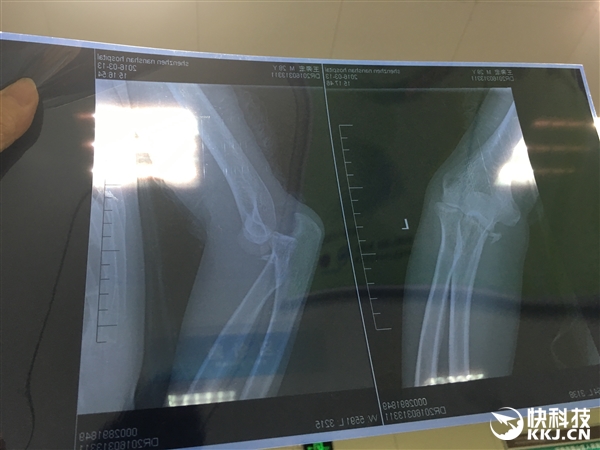

昨日,微博用戶@王奔宏 發帖稱,“人生的第一次住院獻給了小米平衡車”,并展示了自己的住院證明和骨折拍片,再次引發了有關平衡車使用中安全問題的熱議。

雖然他沒有明確事故的具體原因,并未將矛頭直接對準小米平衡車,但作為擁有13萬粉絲的微博簽約自媒體人,此帖發出后還是引來了大量關注。